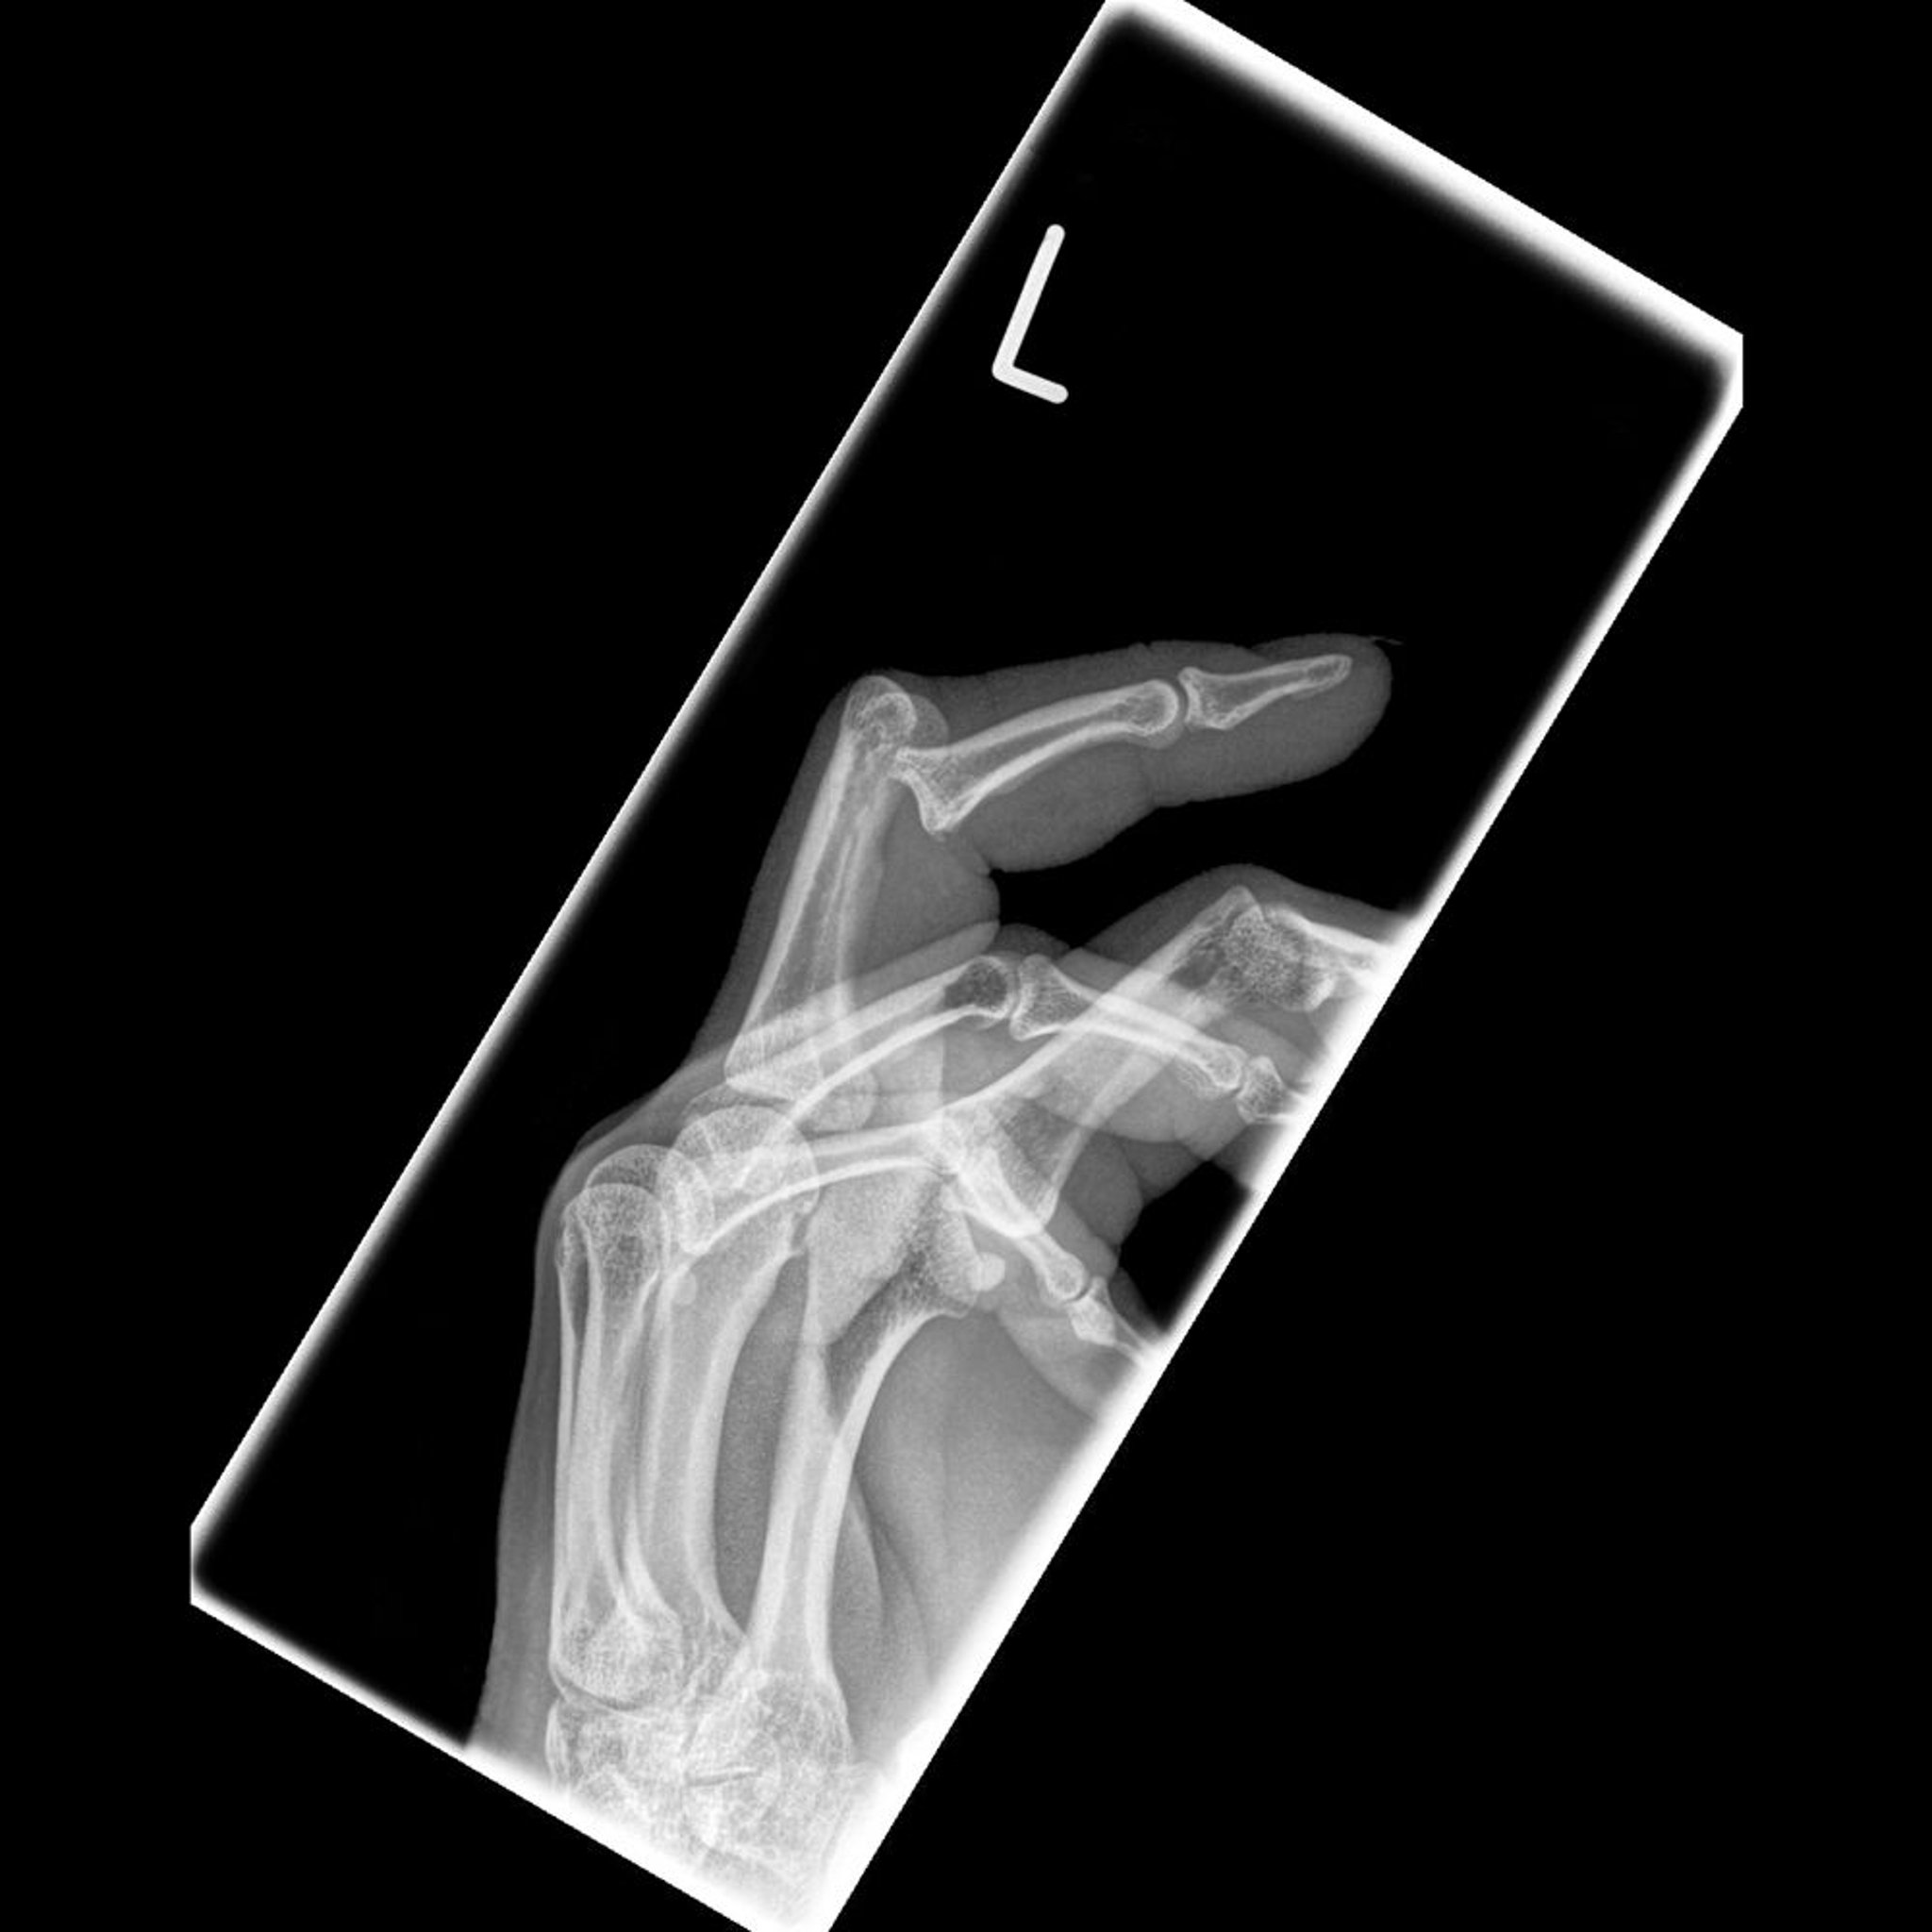

Diese Fotos zeigen eine dorsale Dislokation des proximalen Interphalangealgelenks, begleitet von einem Hammerfinger.

Image courtesy of Danielle Campagne, MD.